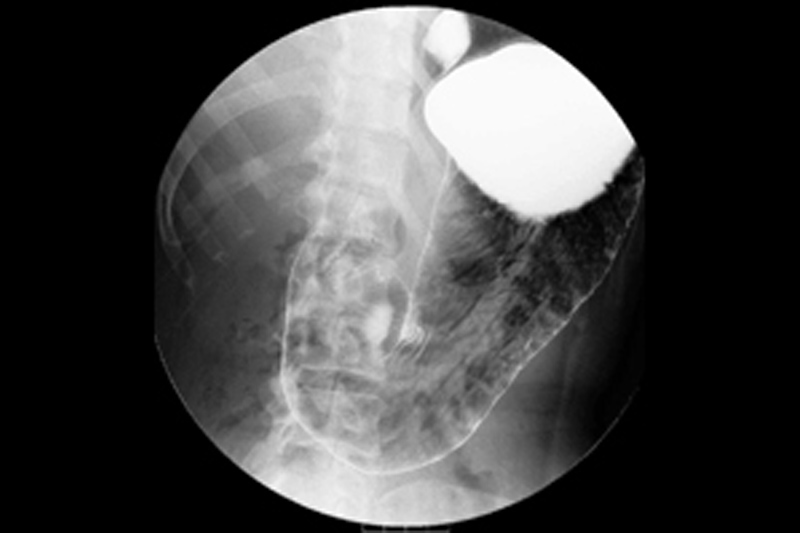

造影剤(バリウム等)を飲んでもらいながら、食道から胃、十二指腸、小腸の形状や粘膜の状態、また通過状態を観察する検査です。検査台の上で身体の向きを変えながら様々な方向から撮影をしていきます。

対象疾患:胃がんや胃潰瘍、逆流性食道炎など。